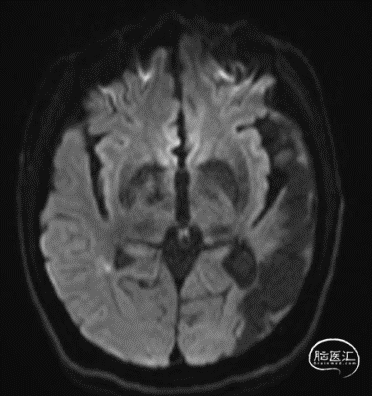

颅脑DWI:右侧脑室旁及基底节区梗塞灶(亚急性期)。

颅脑SWI:左侧颞枕叶软化灶伴微出血灶。

颅脑DWI:左侧基底节、枕顶叶及放射冠区急性梗塞灶。

颅脑SWI:左侧额叶皮层下微出血灶。

斑块分析:左侧大脑中动脉近中段M1段重度狭窄、M1远段-M2分支起始处混合斑块形成,局部管腔闭塞;远端分支较对侧明显减少。

颅脑灌注:左侧部分颞叶、额叶、枕叶及基底节区灌注较对侧减低、延迟。